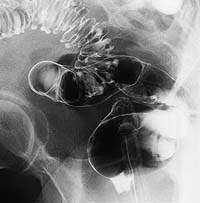

Больной В., 68 лет, поступил в отделение гастроэнтерологии с жалобами на тупые, ноющие боли в животе, преимущественно в левой подвздошной области, вздутие, урчание в животе. Стул - запоры, ощущение неполного опорожнения кишечника. При объективном обследовании отклонений от норм не обнаружено.

При ирригоскопии в области сигмовидной кишки выявлены выпячивания типа «карманов».

При проведении колоноскопии выявлена следующая эндоскопическая картина: